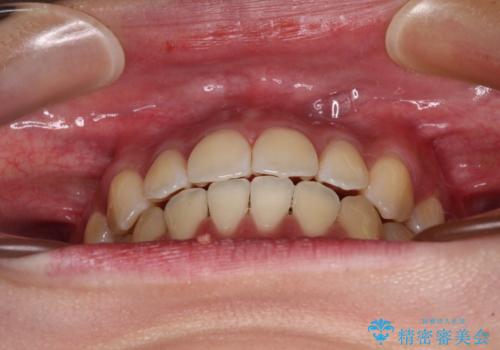

受け口と開咬を急速拡大装置とワイヤー装置で改善

舌の突出癖が開咬の原因であったので、改善のための舌トレーニングを行っていただきました。

舌トレーニングは後戻りにも大きく影響するため、とても重要なトレーニングです。